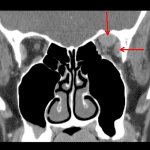

- Enlargement of the left superior muscle complex and lateral rectus muscle with slight stranding about the tendinous insertion of the superior muscle complex

- Slight enlargement of the left lacrimal gland relative to the right

- Orbital pseudotumor aka idiopathic orbital inflammation

Asymmetric enlargement of the left superior muscle complex and left lateral rectus muscle with slight stranding at the tendinous insertion of the superior muscle complex. This appearance is most compatible with orbital pseudotumor (aka idiopathic orbital inflammation), with thyroid ophthalmopathy and orbital cellulitis thought to be less likely. Recommend ophthalmology evaluation.

Slight enlargement of the left lacrimal gland, which can also be seen with orbital pseudotumor.